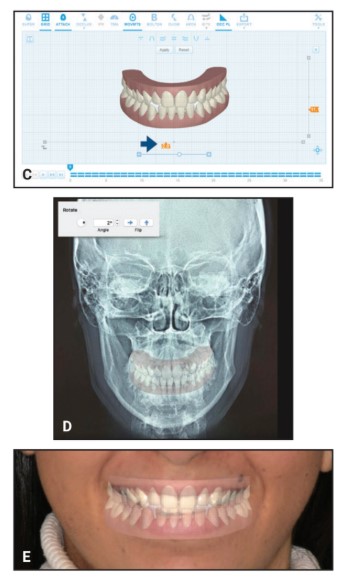

L’articolo descrive una tecnica che affronta una problematica specifica nella pianificazione ortodontica virtuale: l’orientamento del piano occlusale nei software di trattamento digitale.

La metodica proposta prevede:

- L’utilizzo di radiografie laterali del cranio orientate secondo il piano di Francoforte

- Fotografie frontali con retrattori guanciali

- Sovrapposizione del modello digitale alle immagini del paziente

Questa procedura consente di ottenere informazioni più precise riguardo ai requisiti di torque, all’arco del sorriso e alle inclinazioni assiali durante la pianificazione ortodontica.